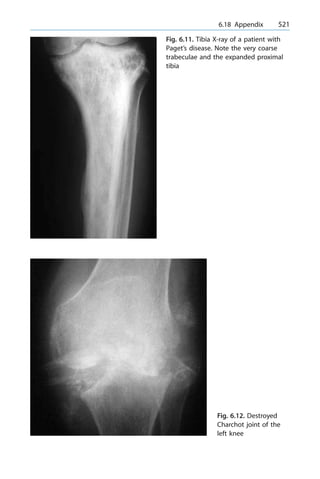

Test

± for the FDS arch 255

± lacterus fibrosis 255

± pronator 255